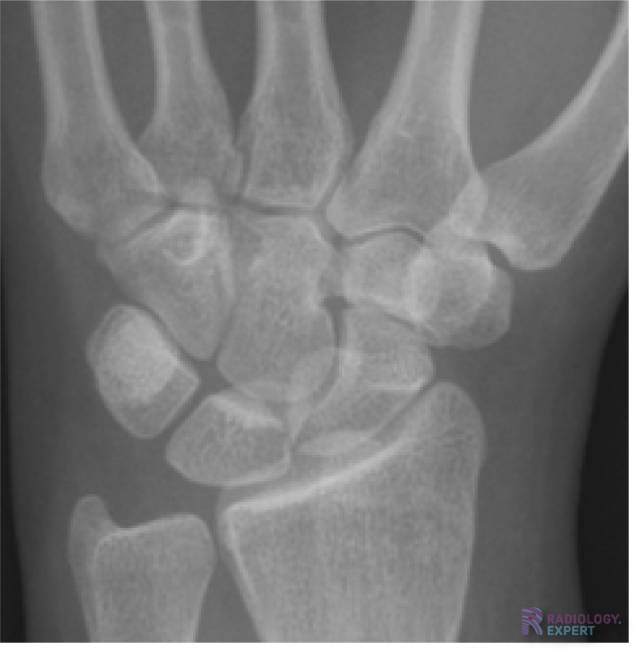

Normale anatomie carpalia. Normale anatomie carpalia.

Klik op afbeelding om overlay te zien